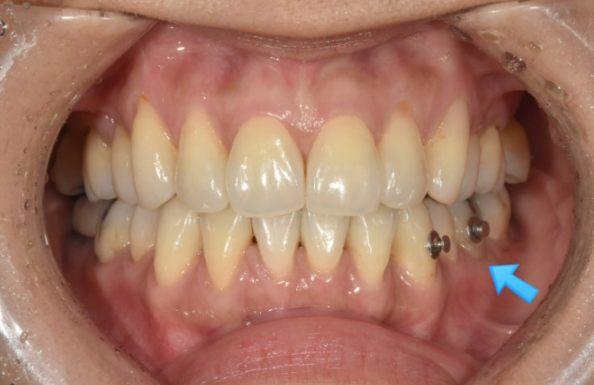

23.06

치료 시작 2개월 후 모습입니다.

2D장치는 뒤에 설측으로 붙여서 앞에는 교정 중인 것이 티가 나지 않습니다.

블랙트라이앵글이 벌써 많이 줄었습니다.

사진에 파란 화살표는 송곳니 뒤쪽 공간이 벌어지지 않게 하는 장치입니다.

앞니 부분교정은 간단해 보이지만, 송곳니 뒤에 공간이 벌어진다던지 하는 부작용을 막기 위해 은근하게 손이 많이 가는 치료입니다.